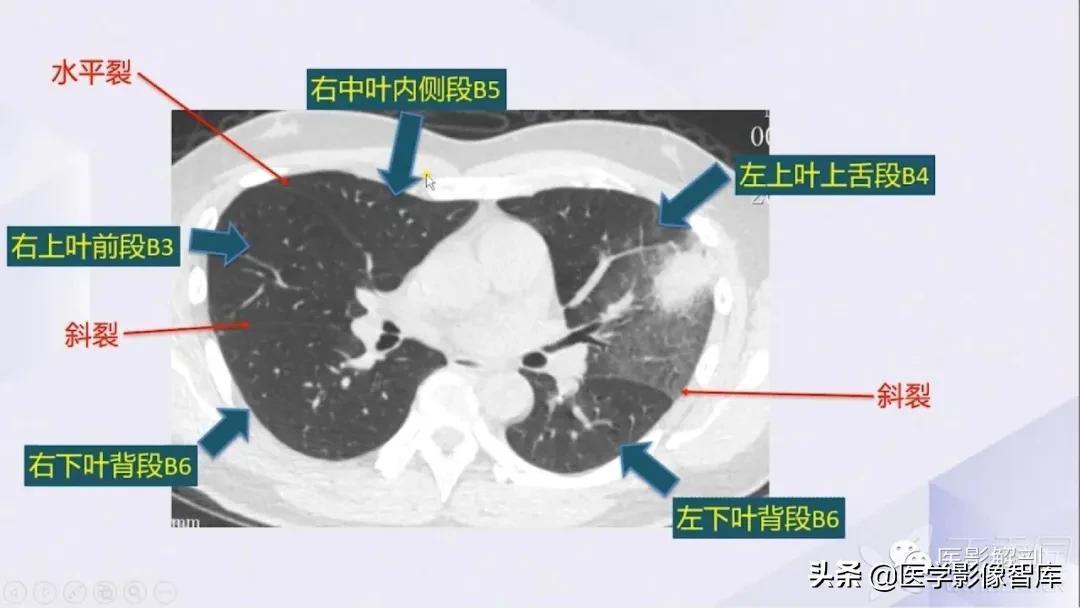

肺部CT解剖(高清图谱)